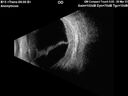

Ruptured Retinal Arterial Macroaneurysm - Submacular hemorrhage and BRAO71 views81 year old female with vision loss for a few days. Coumadin was high with INR at 3.1 VA 6/200Dec 21, 2024